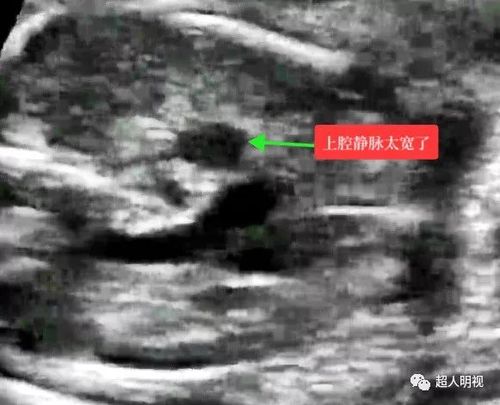

请高度注意胎儿三血管气管切面中上腔静脉之宽度

三血管及气管切面 短轴切面(心室及流出道) 主动脉弓 导管弓 上腔静脉

三血管气管切面异常